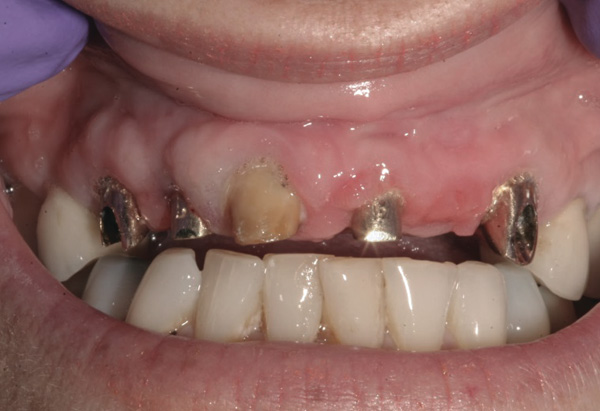

Background: This patient had a failing maxillary dentition and refused to wear a removable prosthesis. A staged approach was employed to retain some of his natural tooth abutments, and recession was noticed at the time of the impression for the second group of implants. Figure 1 shows the patient following insertion of the first set of implant custom abutments; the adjacent natural teeth are still present to support the provisional bridge. Seven months later, as shown in Figure 2, those first-stage custom abutments exhibited evidence of 1 mm to 3 mm of recession.

Results: A decision was made to re-prepare all of the abutments intraorally (Figure 3) so that all abutment margins would be at or below the gingival margin. (Of note, teeth Nos. 8 and 9, also shown in Figure 3, were later submerged for the case to be fully implant-supported.) While re-preparation greatly improved the esthetics of the final result, it required retraction cord placement, new impressions, and new castings.

Figure 1  Patient following insertion of first set of implant custom abutments.

Figure 1

Figure 2 After 7 months, the first-stage custom abutments exhibited evidence of 1 mm to 3 mm of recession.

Figure 2

Figure 3 Abutments re-prepared intraorally.

Figure 3